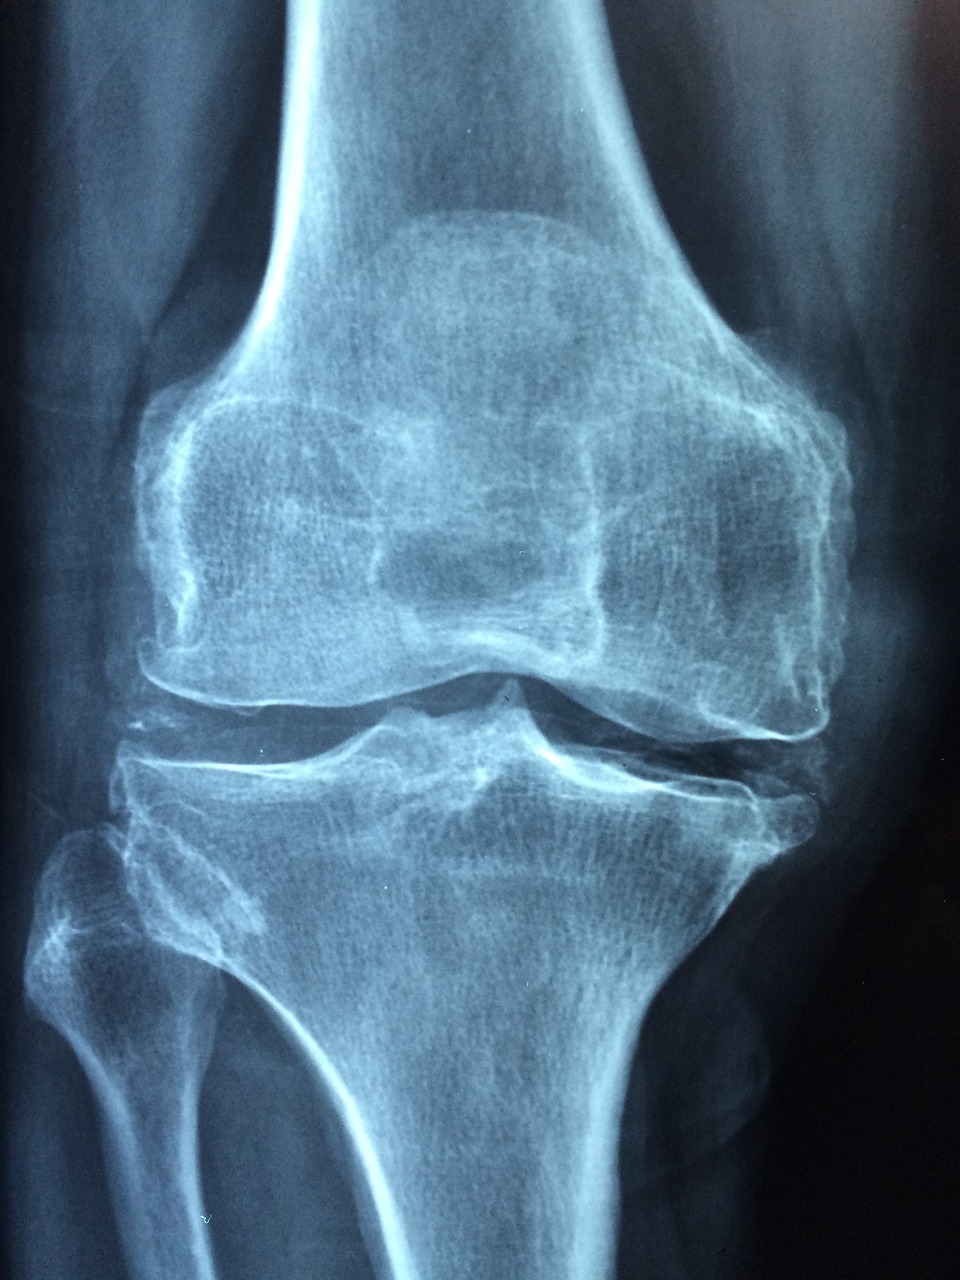

✅ 굽힘 각도(Flexion)의 기준

● 수술 직후: 70~90도 정도

● 2주 차: 90도 이상 확보

● 6주 차: 110도 이상 도달 목표

● 3개월 이후: 120도 이상 유지 가능하면 일상생활에 거의 지장 없음

✅ 폄 각도(Extension)의 기준

● 완전한 폄(0도)을 목표로 합니다.

● 5도 이상 굽혀져 있다면 보행에 지장이 있을 수 있어 추가 운동이 필요합니다.